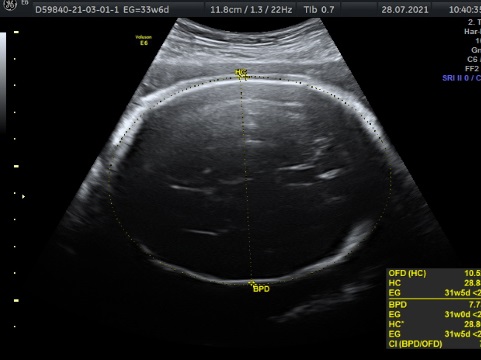

En cualquier semana de embarazo. Es un estudio que nos habla de la oxigenación que esta teniendo tu bebé a través de diferentes flujos sanguíneos ( cordón umbilical, cerebero, arterias uterinas, flujos del corazón. Es un estudio que se realiza para verificar Bienestar Fetal. Tiene una duración de 1 hora y al finalizar el estudio , se realiza 3D, 4D, 5D. Costo $1600